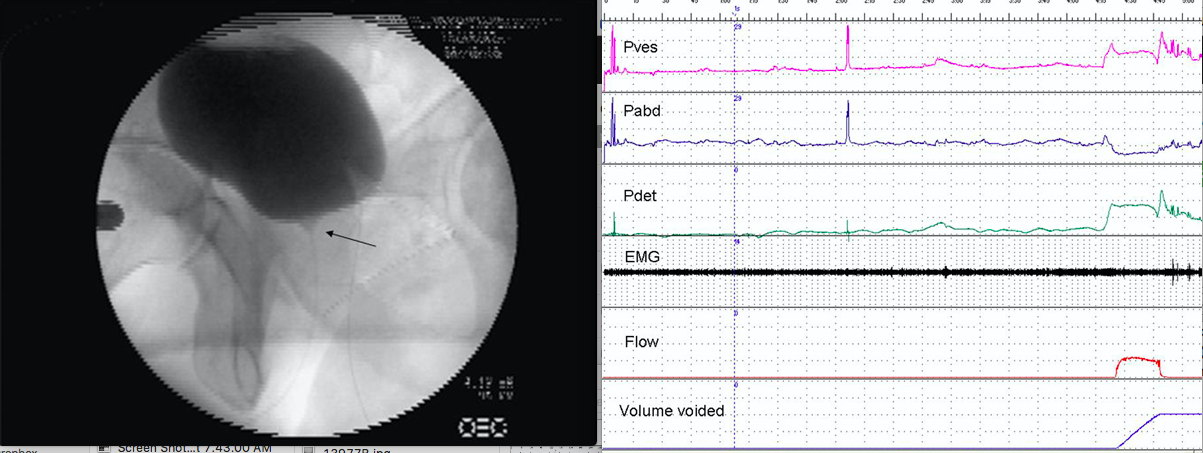

A 52-year-old man with erectile dysfunction undergoes videourodynamics for voiding dysfunction. A videourodynamic image, taken early in filling (at the point indicated by dotted line in the urodynamic tracing), is shown. The videourodynamics suggests a diagnosis of:

4

The cystogram demonstrates an open bladder neck at rest. The urodynamics tracing shows that there was no detrusor activity at the instant the image was obtained. An open bladder neck at rest in a male is highly suggestive of multiple system atrophy (MSA) in the absence of prior prostate surgery. Although other neurological diseases may result in an open bladder neck at rest, none of these are listed except MSA. Erectile dysfunction is often found in MSA, and this finding in concert with the open bladder neck at rest distinguishes this condition from Parkinson’s disease which is often clinically similar in many other respects. Other symptoms of MSA may include other autonomic dysfunctions. Bladder neck dyssynergy would have a closed bladder neck with filling. Cervical spinal stenosis and MS would not typically have an open bladder neck at rest.